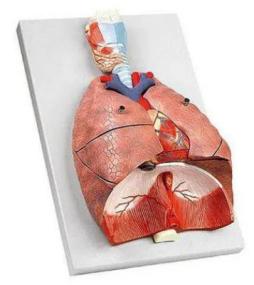

呼吸系统模型

呼吸系统模型